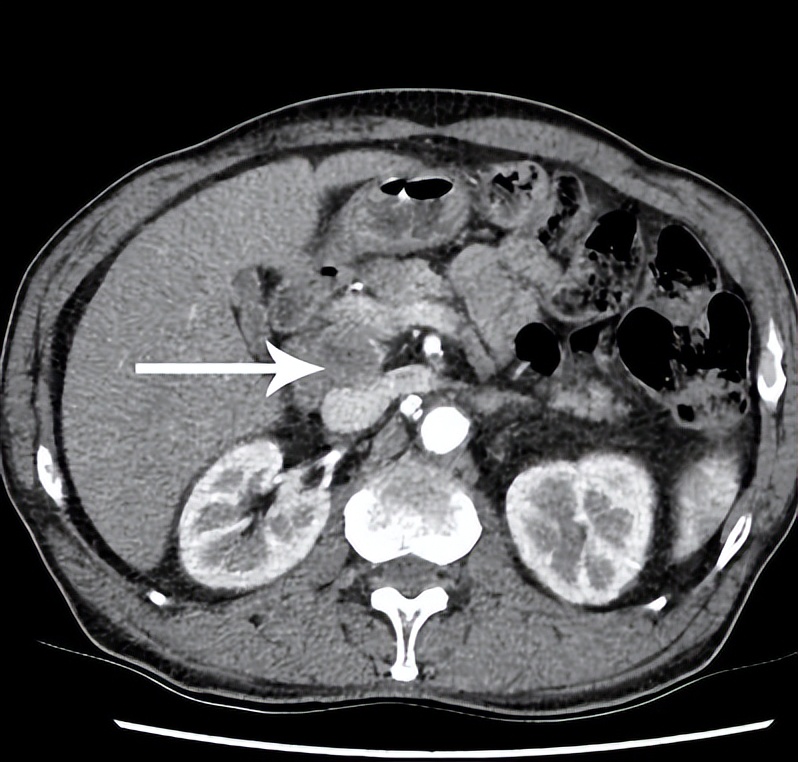

患者,陈某,食管癌动脉化疗栓塞术后2年余,患者复查时发现肝门部淋巴结肿大。为求进一步治疗转移淋巴结,选择放射性粒子植入治疗。

术前CT显示肝门部淋巴结转移瘤的位置(箭头),淋巴结直径大于2cm